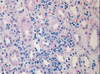

Acute TID; characterized by active inflammation; see eosinophils and lymphocytes (left) and neutrophils (right)

Acute TID; active inflammatory cells in interstitium: lymphocytes, neutrophils, plasma cells, macrophages

Acute interstitial nephritis; infiltration of plasma cells, eosinophils, lymphyocytes, macrophages; also see edema

Acute interstitial nephritis; diffuse infiltration of inflammatory cells; tubules relatively unaffected.